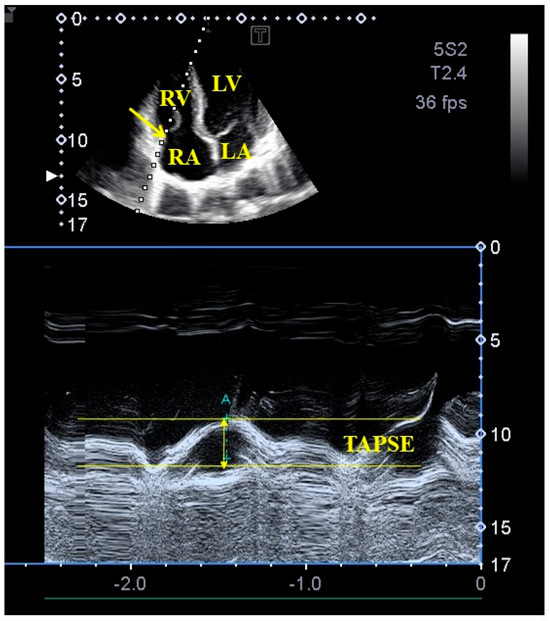

M-mode and two-dimensional Doppler echocardiography: Two-dimensional Doppler echocardiographic examinations were performed in accordance with available professional guidelines and accepted practices. During the examinations, a Toshiba ArtidaTM echocardiography device was used, which could be connected to a PST-30BT (1–5 MHz) phased-array transducer. The person to be examined was asked to lie on their left side, and then, placing the transducer on the chest, measurements were taken from the typical sections from both the parasternal and apical directions. After performing left atrial and left ventricular measurements, the extent of any valvular regurgitation was determined using the continuous-wave Doppler method and visual estimation. Doppler echocardiography was used to exclude significant valvular stenosis as well. LV-EF was determined using Simpson’s method. Representing systolic longitudinal motion of the TA, TAPSE was measured in apical long-axis as a displacement of the lateral edge of the TA toward the apex in systole (Figure 1) [12,17,18].

Figure 1. M-mode echocardiography-derived assessment of tricuspid annular plane systolic excursion (TAPSE) from apical four-chamber view. Abbreviations: LA = left atrium, LV = left ventricle, RA = right atrium, RV = right ventricle, TAPSE = tricuspid annular plane systolic excursion.